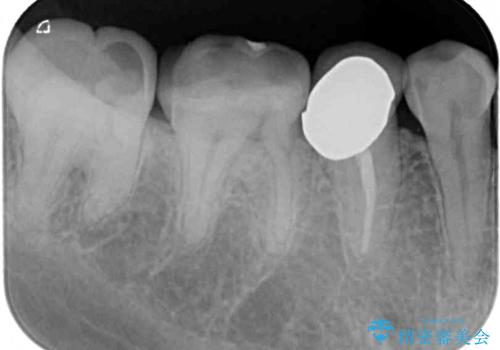

- 奥歯が欠けてしまった事を主訴として来院した患者様です。

頬側の欠けている範囲が大きく、以前治療した詰め物も大きいため、詰め物を外してむし歯を除去し、

形を整えて一度仮歯に置き換え、フルジルコニアクラウンにて補綴しました。

高強度のフルジルコニアクラウンは、強いかみ合わせでも壊れにくいです。

また審美的にも満足していただけました。